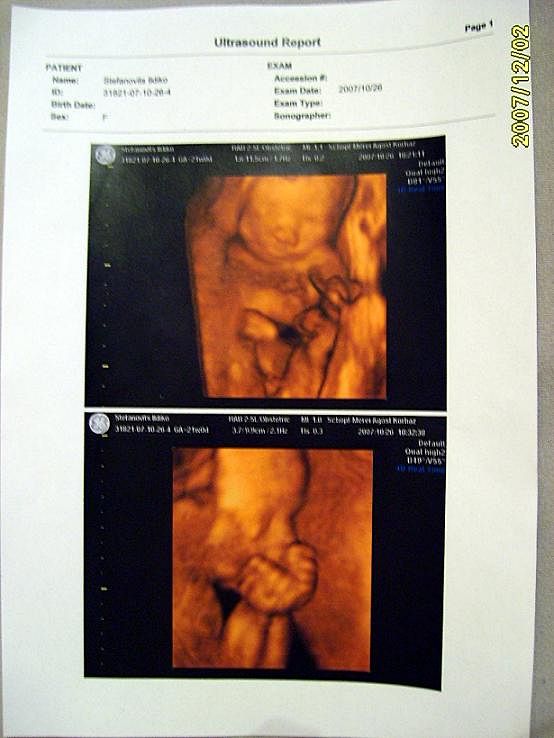

4D Ultrahang - 21+1 (07/10/26, Bp.)

Kinyomtatott képek 1